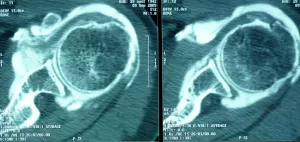

Bilan préopératoire ou Comment faire le diagnostic

L’examen clinique complet du patient par votre médecin permet d’évoquer le diagnostic (douleurs d’épaule nocturnes…), d’éliminer des lésions associées (fracture, capsulite rétractile,…) et de proposer un bilan complémentaire adapté (radiographie, échographie, arthro-scanner, IRM, arthro-IRM, électromyogramme).

Lorsqu’il existe une rupture de la coiffe des rotateurs, l’étendue des lésions dans le plan frontal (distale, intermédiaire ou rétractée à la glène), dans le plan sagittal (rupture complète ou incomplète, nombre de tendon atteint ; si ≥ 2 tendons = rupture massive), en épaisseur (rupture transfixiante ou partielle ; face profonde ou superficielle) doit être décrite de manière précise.

Par ailleurs, le bilan apprécie la qualité osseuse (ostéoporose, lacune osseuse) et musculaire (infiltration graisseuse).